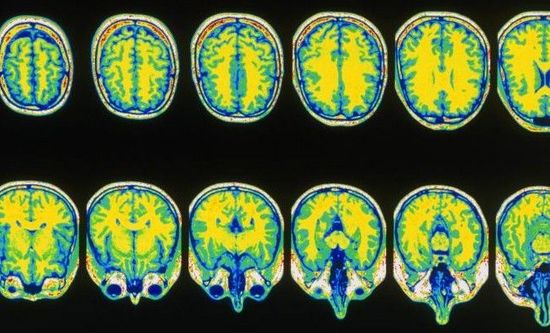

通过使用功能性磁共振成像(fMRI),在以色列特拉维夫的研究人员们会分别观察健康人以及植物人的大脑活动。首先,他们会展示出两组陌生人的照片,之后是熟悉面孔的照片。而处于植物状态患者们的大脑活动模式则会与健康受试者们的大脑模式进行比对。

然而,功能性磁共振成像是一种准确的、可靠的测试,它可以告诉医生,病人大脑中的哪些区域是活跃的。但“活跃”实际上所代表的意义同样也有些模糊。“对于这些研究,我们应该持有乐观的态度,但是同时也需要谨慎行事。”赫希说。